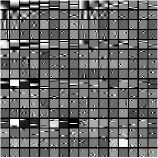

Fig. 1 shows example transforms (rows of are reshaped as patches and the first slices of such 3D patches are shown) learned from patches of an XCAT phantom [54] volume. The transform learned with in (P0) has more oriented features whereas the transform learned with shows more gradient (or finite-difference) type features (pointed by the green arrows). This behavior suggests that a single ST may not be rich enough to capture the diverse features, edges, and other properties of CT volumes. Therefore, next we consider the extension of the ST approach to a rich union of learned transforms scheme.

Fig.Β 3 presents an example of the pixel-level clustering in the central axial slice achieved with the PWLS-ULTRA method for . Since PWLS-ULTRA clusters patches, we cluster individual pixels using a majority vote among the 3D patches that overlap the pixel. Class contains most of the soft tissues; class comprises most of the bones and blood vessels; classes and have some high-contrast edges oriented along specific directions; and class mainly includes low-contrast edges. Since the clustering step (during both training and reconstruction) is unsupervised, i.e., different anatomical structures were not labeled manually, there are also a few edges with high pixel intensities included in class . The trained (3D) transforms (with ) for each cluster are also displayed in a similar manner as in Fig.Β 1. The transforms show features (e.g., with specific orientations) that clearly reflect the properties of the patches/tissues in each class.

Recall that in Section IV.F, we used the transforms learned from the patches of the XCAT phantom volume to perform reconstruction of the chest volume from helical CT data. Alternatively, one could learn the transforms from the patches of the PWLS-EP reconstruction of the helical CT data. Fig.Β 14 shows the union of transforms () learned from patches of the XCAT phantom and the PWLS-EP chest reconstruction, with . These two union of transforms display some similar types of features, and provide similar visual reconstructions in PWLS-ULTRA (with patch-based weights ) in Fig.Β 14. Thus, the transform learning algorithm extracts quite general and effective sparsifying features for images, without requiring a very closely matched training dataset.